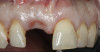

(13.) Postoperative image of site No. 8 taken 4 months after extraction and grafting.

Figure 13